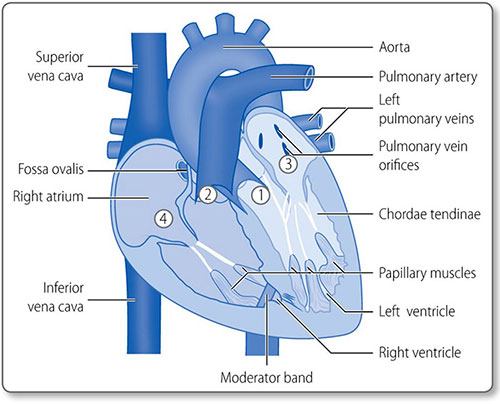

HEART

The heart is composed of muscle arranged around a framework of fibrous tissue and is the size of a fist. The two atria collect blood and fill the two ventricles, which pump blood into the pulmonary and systemic circulations (Figure 1.2). Its four valves prevent blood flow in the wrong direction.

Chambers and valves

The heart has four muscular chambers, each connected to a great vessel. The four valves lie between the ventricles and atria and the ventricles and the great arteries (Figure 1.5).

Left atrium

The mitral orifice and valve separate the left atrium and ventricle. The atrium receives its blood supply from the left circumflex coronary artery. The left atrial appendage or left auricle is a muscular out-pouching continuous with the left atrium. The left and right atria are separated by the interatrial septum.

Mitral valve

The mitral valve prevents blood regurgitating back into the left atrium during systole. It has two leaflets (i.e. it is bicuspid):

- The anterior leaflet attaches to the anterior aspect of the mitral orifice

- The posterior leaflet attaches to the posterior orifice

The free edges of the leaflets are attached to the chordae tendinae, which attach to the left ventricular papillary muscles. This subvalvular apparatus prevents valve prolapse during systole.

Left ventricle

The left ventricle is an elongated inverted cone that 5is circular in cross-section (Figure 1.6). Its internal surface is heavily trabeculated by muscle fibers (Figure 1.7).

The mitral valve chordae tendinae attach to an anterior and posterior papillary muscle.

Figure 1.5: Anatomy of the heart valves. ① Aortic valve. ② Pulmonary valve. ③ Mitral valve. ④ Tricuspid valve.

Figure 1.7: An exploded view of the left atrium (LA) ①, left ventricle (LV) ② and mitral valve ③. The left atrial appendage ④ orifice and a pulmonary vein ⑤ are visible in the LA. Trabeculations of the LV are coarser than those of the right ventricle ⑥. The mitral valve leaflets ③ are tethered to the papillary muscles ⑦ by the chordae tendinae. Courtesy of Dr K Suvarna.

8Blood enters the left ventricle through the mitral valve and exits via the aortic valve. The outflow tract is posterior to the right outflow tract, which ‘wraps’ around the aorta. Blood supply is from the left anterior descending (LAD) artery and its diagonal branches.

Right atrium

9The right atrium receives deoxygenated blood from the superior and inferior venae cavae and coronary venous blood through the coronary sinus. The smooth posterior surface is separated from the trabeculated anterior surface by the crescent-shaped crista terminalis muscle.

The trabeculated right atrial appendage – the auricle – projects from the superoanterior segment of the atrium.

Tricuspid valve

The tricuspid valve has anterior, posterior and septal leaflets. Their free edges are attached to the ventricular walls by the chordae tendinae and papillary muscles, which are smaller than the left subvalvular apparatus.

Right ventricle

The right ventricle, like the left, is an elongated inverted cone shape, but operates at a much lower pressure. As a result, the left ventricle and interventricular septum bulge into the right ventricular cavity (Figure 1.6).

The moderator band is a ridge of muscle that extends from the septum to the anterior wall at the base of the papillary muscle. It is part of the electrical conduction pathway that ensures the right-sided papillary muscles contract before the ventricle does, to ensure the tricuspid valve is braced for systole.

Pulmonary valve

The pulmonary valve is a tricuspid, semilunar valve at the apex of the right ventricular outflow tract.